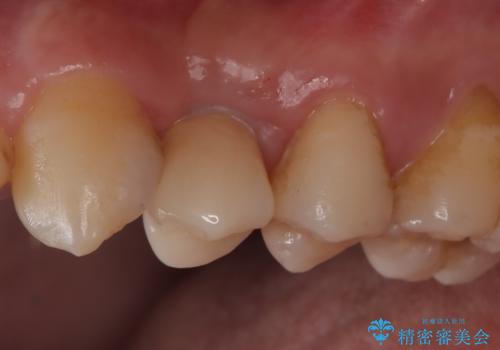

- 440,000円(インプラント体220,000円+カスタムアバットメント110,000円+オールセラミッククラウン110,000円)費用は治療当時の料金となります

長い間虫歯を放置していたため、根っこだけになっている状態でした。このままでは被せ物を被せられないため抜歯を行い治癒を待った後にインプラントを埋入しオールセラミッククラウンで治療を行いました。